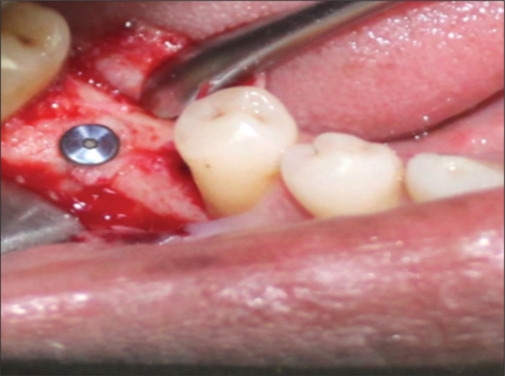

Background: To minimize the risk of impaired osseointegration historically, it has been recommended to insert the implant into the bone (submerged implants) and to allow for submerged healing of 3-6 months in the lower and upper jaw, this conventional technique is advocated. The concept of nonsubmerged healing was introduced in 1988 in which gingival former was placed at the time of implant placement instead of cover screw. The treatment concept of nonsubmerged implant placement enables early implant loading, one surgical procedure only, and a reduced treatment period for the patients.

Materials and method: A prospective split-mouth study of a minimum of 20 bilateral edentulous patients (total of 40 sites) was selected and randomly distributed in two groups: submerged and nonsubmerged implants. Patients were evaluated clinically and radiographically by assessing the patients on clinical parameters which included peri-implant probing depth, mucosal thickness, and width of keratinizing gingiva. Radiographic parameters were crestal bone height-distance between implant shoulder and alveolar crest compared from the bone level, on intraoral periapical.